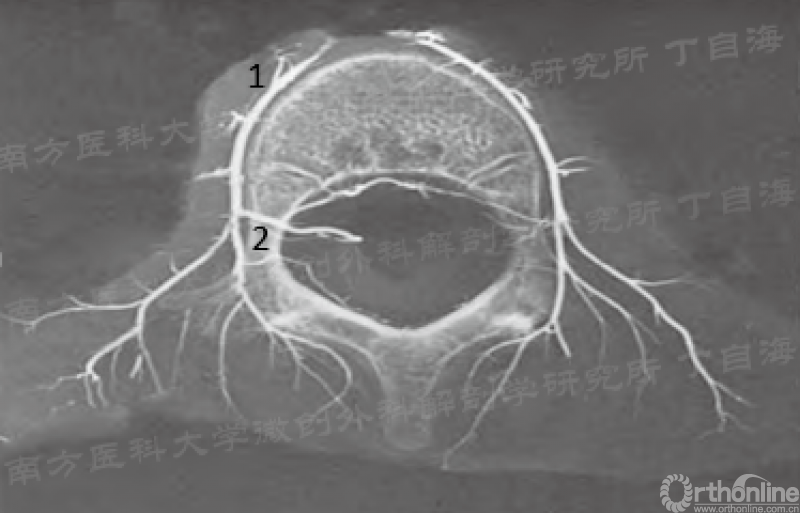

椎间孔动脉的来源和走行(1.腰动脉 2.椎间孔动脉)